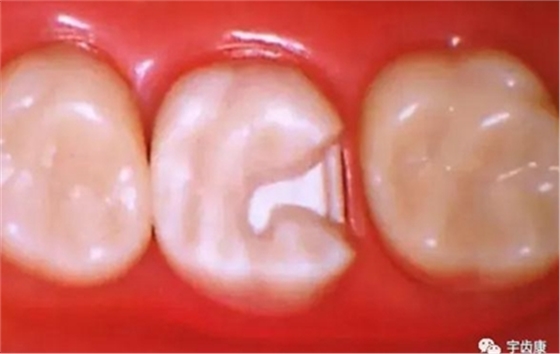

箱型固位形

3.基牙具有良好的抗力形

保留較多的牙體組織

增加牙體抗力形的措施